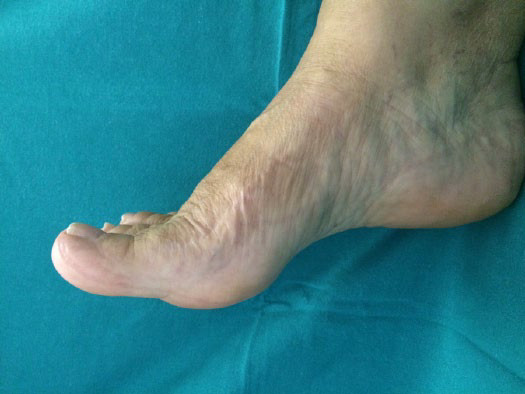

Risultato dopo 2 anni. Buona dorsiflessione attiva e ottimo recupero funzionale